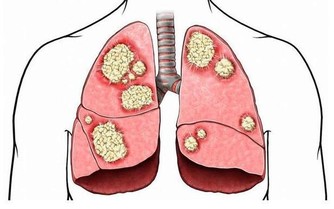

●肺經一通,感冒不來!肺經到底在哪裡?知名的中西醫師林燦城,節目中當場畫給你看!還有一套拍打肺經運動,促進肺部氣血循環,預防感冒!

●林燦城醫師還要送給聚焦2.0鐵粉兩個大禮包!感冒初期喉嚨痛,快喝"桑菊飲",鼻塞時,還有一道獨家秘方"鵝不食草中藥粉鼻噴劑"!